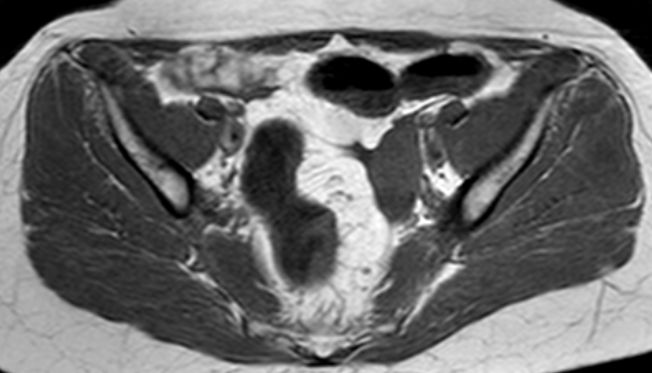

73-jährige Frau mit Ascites, Pleuraerguss links und Unterbauchtumor.  Das Netz ist komplett in einen Omental-Cake umgewandelt. An der Zwerchfellkuppe miliare Tumoraussaat.

Histologisch solide, angedeutet papillär strukturierte Tumorzellproliferaten. Vergrößerte hyperchromatische Zellkerne mit Kerneinbuchtungen, erhöhter mitotischer Aktivität. Zytoplasma verbreitert, optisch leer.

Beide Adnexe in knapp kindskopfgroße blumenkohlartige Tumoren umgewandelt.

Im Douglas finden sich pararektal mehrere bis zu pflaumengroße Tumorknoten.